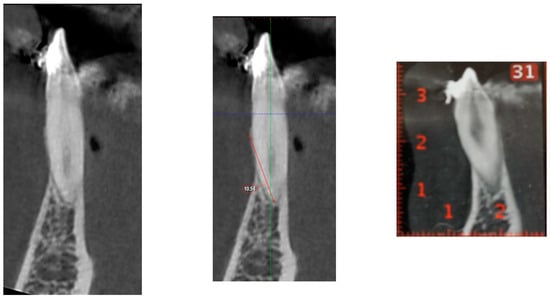

The observed variability in the data was also notable, with standard deviation values ranging between −2.86 mm and 3.51 mm. This range indicates that in specific samples, the actual difference in measurements could be as high as 7 mm. This discrepancy is clinically significant even in patients with healthy periodontal support, as it could result in misjudgment of the alveolar bone condition. To illustrate this point, Figure 1 highlights a case where the measurements from the DICOM and PDF files were relatively similar, showing minimal differences. In contrast, Figure 2 shows a case where the discrepancy between the two modalities reached a mean difference of 9 mm. Differences of this magnitude could drastically alter the treatment plan, potentially leading to over- or underestimation of periodontal health and bone support.

Figure 2.

Compared with that in the PDF, the height of the buccal bone in the 3D DICOM is much greater.